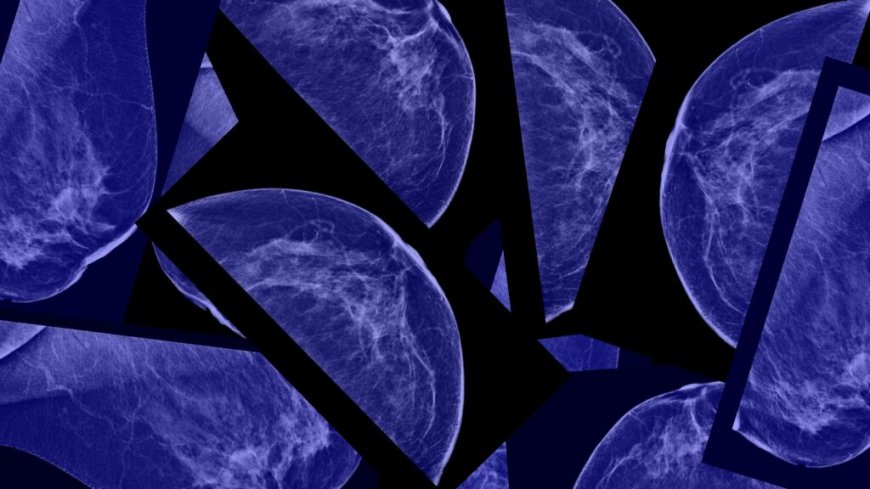

How mammograms could transform to predict the future